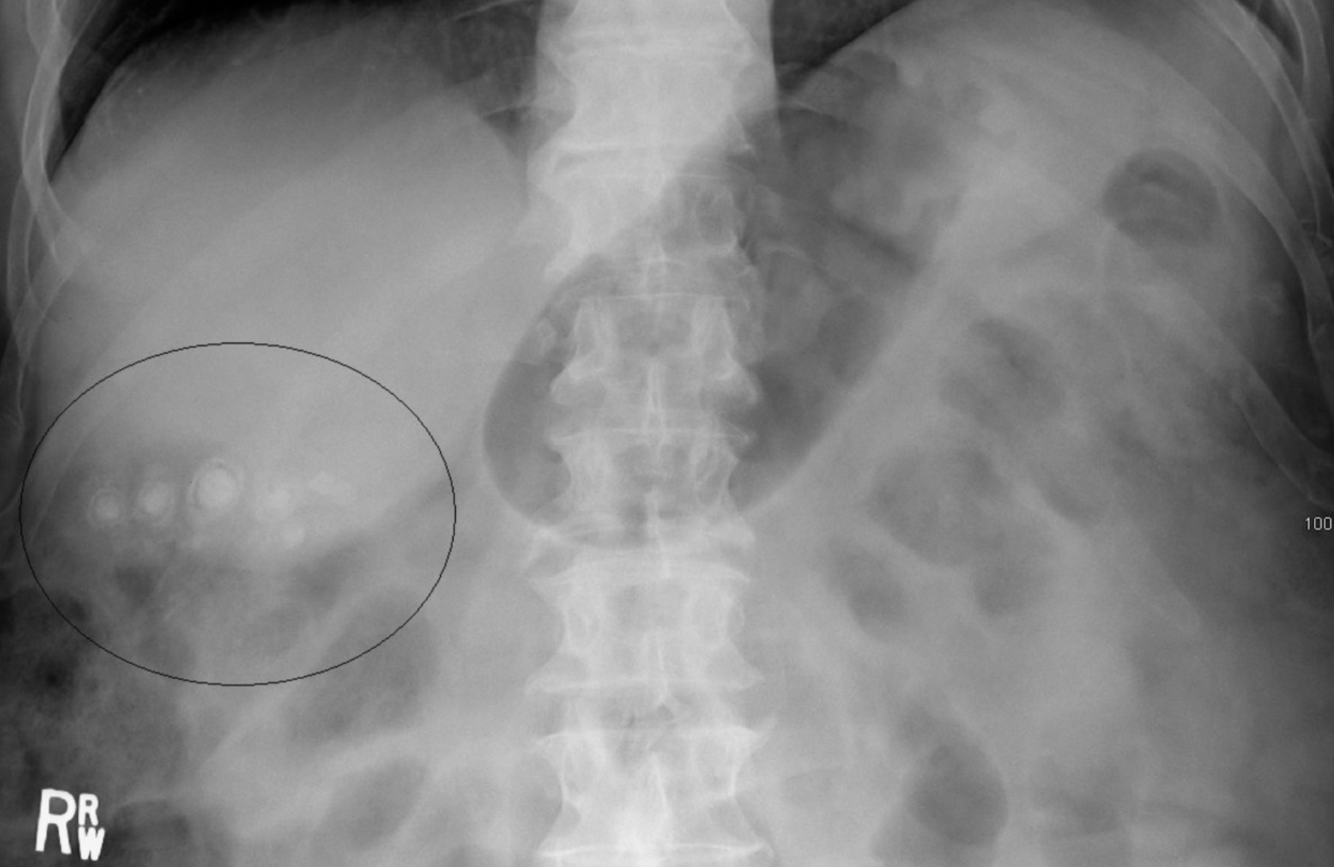

Calculs de la vésicule biliaire

Radiographie de l’abdomen (vue AP ; décubitus dorsal)

Plusieurs structures calcifiées arrondies sont visibles dans le quadrant supérieur droit (cercle noir). Beaucoup ont un aspect feuilleté, avec une calcification centrale dense (verte) entourée d’un anneau intérieur clair et d’un anneau extérieur calcifié (contour blanc).

Les calculs de cholestérol pur, le type le plus courant de calculs biliaires, sont radiotransparents sur les radiographies abdominales. Le pigment noir et les calculs biliaires mixtes peuvent contenir suffisamment de calcium pour être radio-opaques.